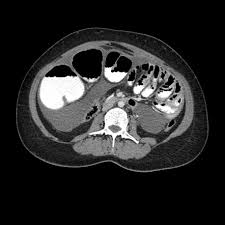

Focused abdominal sonography for trauma revealed trace free fluid (FF) in the pelvic cul-de-sac. No evidence of injury by computed tomography and clinical course. Trace FF (arrow) in pelvis and urinary Obstetrics and Gynecology